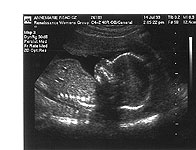

Layer 5 Layer 5 Layer 4 Layer 4 Pregnant Anne Photo

Pregnant Anne Photo